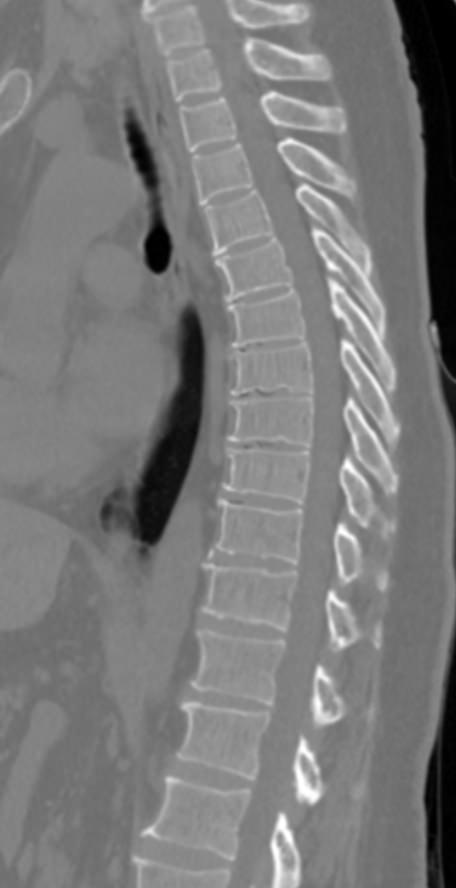

Для диагностики даже незначительных патологических изменений в различных отделах позвоночника, особенно в случае распространенного поражения, применяется один из современных наиболее информативных методов обследования – мультиспиральная компьютерная томография всего позвоночника. Методика основана на использовании проникающей способности рентгеновских лучей через органы и ткани человека и позволяет получить подробное изображение всех структур позвоночного столба. В комплексное обследование входит исследование шейного, грудного, пояснично-крестцового отделов позвоночника и копчика.

В медицинских центрах «Доступная медицина» сканирование всего позвоночника выполняется на новейших мультиспиральных компьютерных томографах последнего поколения TOSHIBA AQUILION в различных модификациях. Особенностью данных аппаратов является их способность проводить от 64 до 128 тончайших срезов одномоментно с минимальной толщиной от 0,5 мм.

Увеличенное количество высокочувствительных детекторов, которыми оснащены томографы, позволяет получать послойные снимки высокого качества с большой скоростью. Эта особенность данных аппаратов обеспечивает быстроту выполнения сканирования. При этом пациент получает минимальную дозу облучения, что имеет важное значение, особенно при такой обширной зоне исследования, как позвоночный столб.

- дегенеративно-дистрофические заболевания позвоночника (остеоартроз, спондилез, деформирующий спондилоартроз);

- травматические повреждения позвоночника (компрессионные и оскольчатые переломы);

- стеноз (сужение) позвоночного канала;

- грыжи межпозвонковых дисков (протрузии, экструзии и грыжи Шморля);